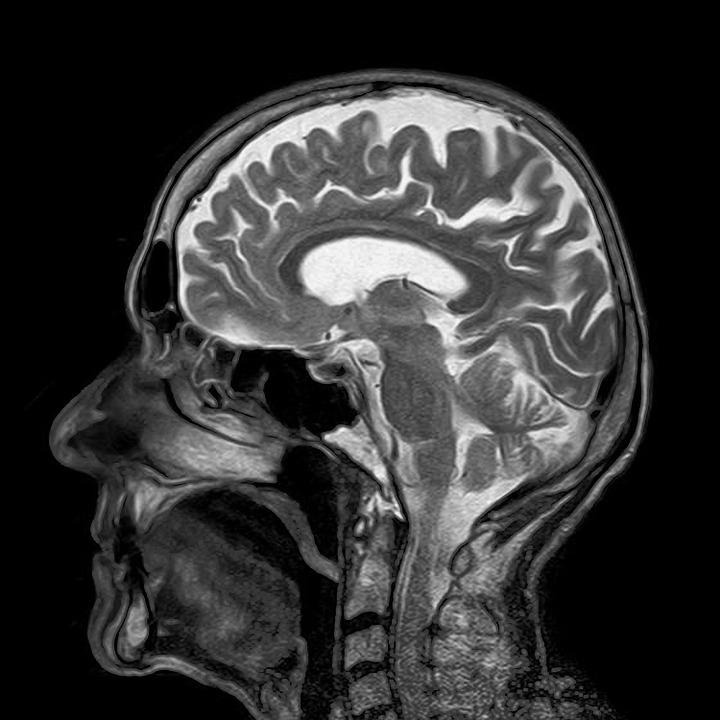

МРТ головного мозга: показания и результаты

Раздел: Визуальный дайджест